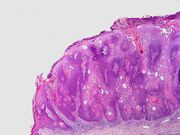

Micrograph of a seborrheic keratosis (H&E stain, scanning magnification)

Visual diagnosis is made by the "stuck on" appearance, horny pearls or cysts embedded in the structure. Darkly pigmented lesions can be challenging to distinguish from nodular melanomas.[10] Furthermore, thin seborrheic keratoses on facial skin can be very difficult to differentiate from lentigo maligna even with dermatoscopy. Clinically, epidermal nevi are similar to seborrheic keratoses in appearance. Epidermal nevi are usually present at or near birth. Condylomas and warts can clinically resemble seborrheic keratoses, and dermatoscopy can be helpful to differentiate them. On the penis and genital skin, condylomas and seborrheic keratoses can be difficult to differentiate, even on biopsy.[citation needed]

A study examining over 4,000 biopsied skin lesions identified clinically as seborrheic keratoses showed 3.1% were malignancies. Two-thirds of those were squamous cell carcinoma.[11] To date, the gold standard in the diagnosis of seborrheic keratosis is represented by the histolopathologic analysis of a skin biopsy.[12]